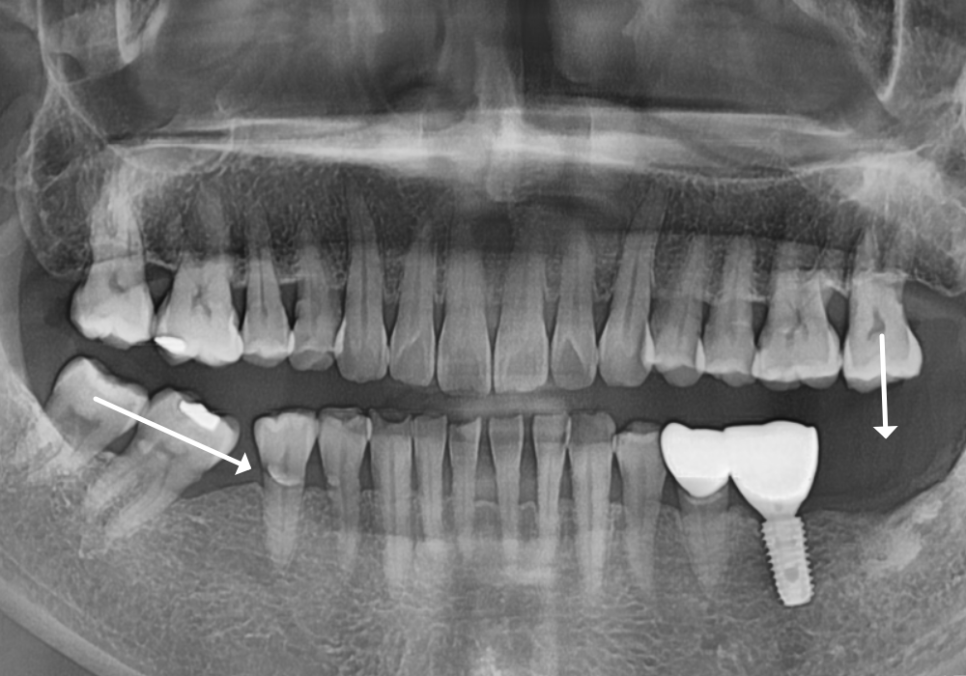

오른쪽 아래(#46)와 왼쪽 아래 맨 끝(#37)

치아를 발치한 지 꽤 오래된 상태였죠.

| 1) 오른쪽 어금니#47,48 어금니들이 빈 곳으로 많이 쏠려 #46 상실 부위에 임플란트를 심을 공간이 부족한 상태2) 왼쪽 어금니위쪽 어금니(#27)가 맞물릴 곳이 없어 아래로 정출되어 내려온 상태 |